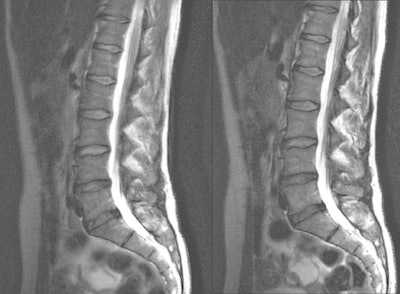

| The lumbar spine of a 68-year-old woman with sequestered disk herniation is shown in parallel transmission mode (right) and single-source transmission mode (left). Independent readers rated the parallel image as superior. Images courtesy of Radiology (December 2010, Vol. 257:3, pp. 743-753). |

Spinal 3-tesla MRI with parallel transmission also yielded a median assessment of at least adequate image quality in all of the compared sequences. There were no cases in which an image was determined to be of nondiagnostic quality.

With the "significant acceleration" of scan time and parallel transmission with 3-tesla MRI of the spine, Nelles said, there is "really a strong advantage for patients with back pain and in cases of claustrophobia. The diagnostic image quality of these fast sequences stays comparable to that of the single standard transmission sequences."